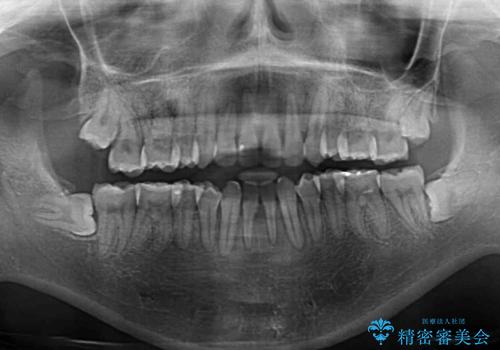

後戻りの再矯正 ワイヤー装置でデコボコと隙間を改善

- 学生時代の抜歯矯正の後戻りが気になり、再矯正を希望して来院された患者様です。

マウスピース矯正は継続する自信がなく、気になるところを短期間で改善したいとのことで、ワイヤー装置にて矯正治療を行うこととしました。

詰め物で隠していた下顎前歯の隙間は、歯軸を改善することで詰め物を除去しても隙間が目立たなくなりました。

まだ改善したいところはありましたが、患者様自身は大変満足されたとのことで、治療を終えることとなりました。